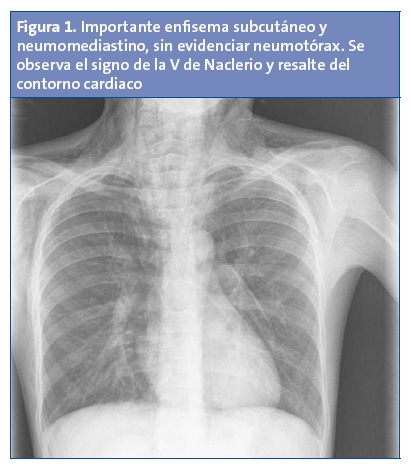

Niño de 12 años, con antecedente de asma bronquial intermitente sin tratamiento de base, que acude a la consulta de Pediatría de su centro de salud por la aparición brusca de un edema cervical, disfagia y dolor torácico desde esa mañana (aproximadamente seis horas de evolución), en el contexto de una crisis asmática que el niño estaba tratando con salbutamol inhalado en su domicilio. A su llegada presenta un regular estado general, palidez cutánea, taquipnea y tiraje intercostal; con hipoventilación generalizada en la auscultación. Se observa un edema a nivel cervical bilateral, con crepitación en dicha zona. Ante crisis asmática con score moderado se inicia tratamiento broncodilatador y corticoideo y se deriva a Urgencias hospitalarias. Allí realizan una radiografía de tórax, encontrando neumomediastino y un enfisema subcutáneo torácico y cervical, sin neumotórax (Fig. 1). Se pauta analgesia y tratamiento con oxígeno, broncodilatadores y prednisona oral; experimentó mejoría progresiva, dándole de alta cuatro días después.

La radiografía de tórax habitualmente es suficiente para el diagnóstico (aproximadamente en un 69% de los casos)7. Los hallazgos clásicos8 son el signo del diafragma continuo (presencia de aire entre el pericardio y el diafragma), el signo de la V de Naclerio (presencia de aire entre la aorta descendente y el hemidiafragma izquierdo), el resalte del contorno cardiaco (por la presencia de aire mediastínico) y la existencia de enfisema subcutáneo. No se precisan otras técnicas de imagen de forma rutinaria.